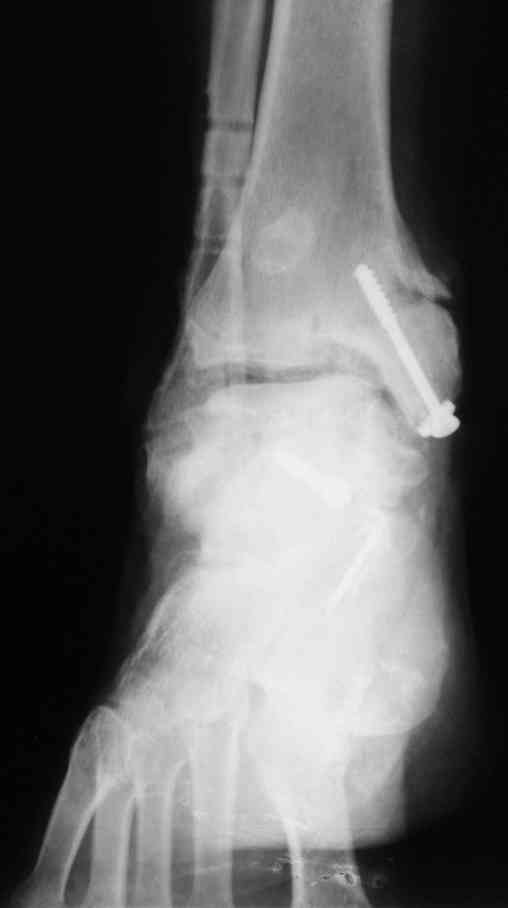

Имя     : отдал период.jpg

Тип     : image/jpeg

Размер  : 15231 байтов

Описание: отсутствует

Url     : http://weborto.net:8080/pipermail/ortho/attachments/20070616/4aa8531d/attachment-0007.jpg

В Вашей ситуации мы произвели открытую репозицию и фиксацию

металлоконструкциями. Все зажило первично, посттравматического

дефартроза избежать не удалось. Пациент от артродезирующих операций в

отдаленном периоде отказался.